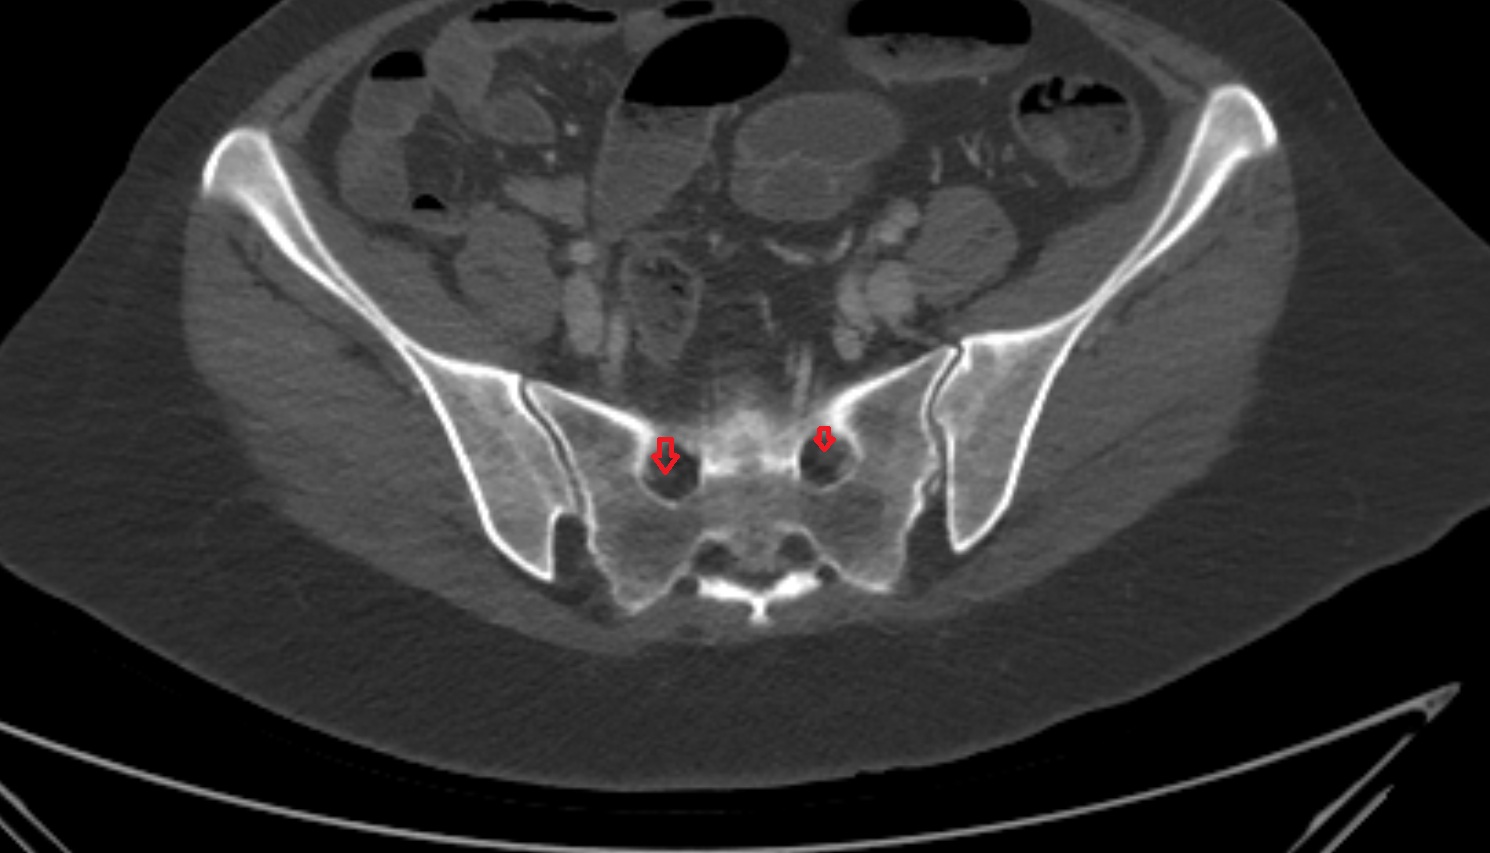

- Sacroiliac joint